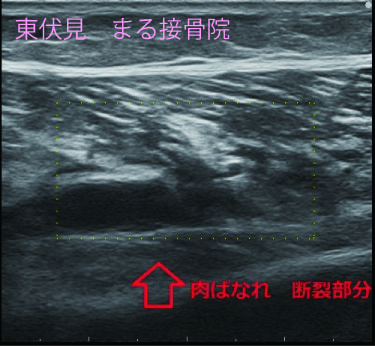

下のエコー画像、ふくらはぎの筋腹内に断裂部分(空洞部分)が診られ、特殊な撮影方法で出血度合も確認できます。

エコー検査は筋肉の状態を正確に確認でき、的確に治療をできます。